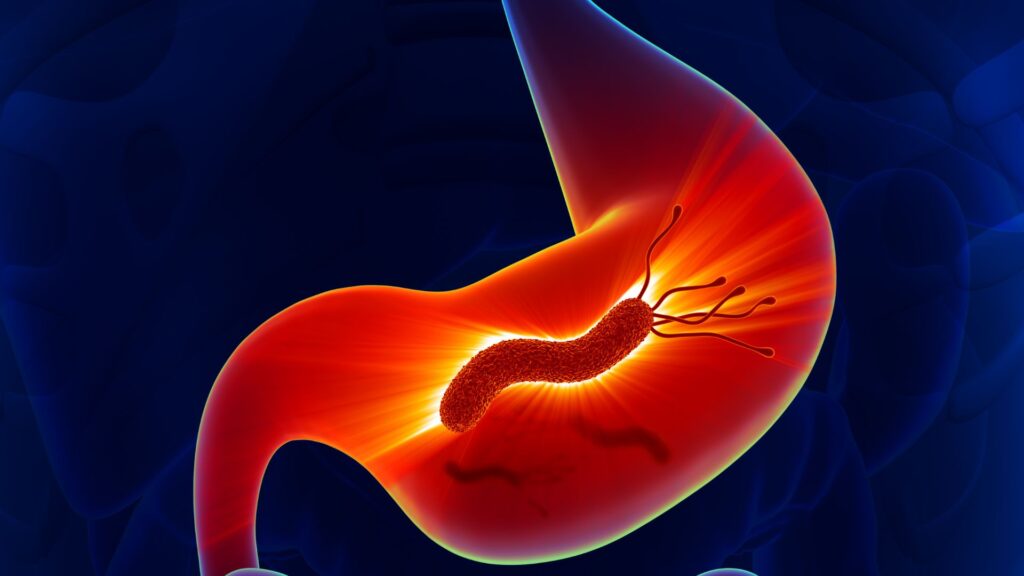

Más allá del estómago

La asociación entre Helicobacter pylori y el espectro de cánceres digestivos. Esta revisión analiza el papel emergente de Helicobacter pylori más allá del estómago, destacando su asociación con distintos tipos de cánceres digestivos como el hepático, biliar, esofágico, colorrectal y pancreático. Aunque es un carcinógeno gástrico bien establecido, cada vez hay más evidencia que lo vincula con neoplasias extragástricas a través de mecanismos como la inflamación crónica y la acción de factores de virulencia. La solidez de estas asociaciones varía según el tipo de cáncer, siendo más consistente en los casos de cáncer hepático y biliar. Les invitamos a leer el artículo «Beyond the stomach: the association between Helicobacter pylori and the spectrum of digestive cancers», que explora el vínculo emergente entre H. pylori y diversos cánceres digestivos extragástricos. Un recurso esencial para actualizar su conocimiento sobre el impacto de esta bacteria en el cáncer hepático, biliar, esofágico, colorrectal y pancreático. 👉 ¡Acceda al artículo completo y profundice en los mecanismos subyacentes y las implicaciones terapéuticas! https://pubmed.ncbi.nlm.nih.gov/40964055/